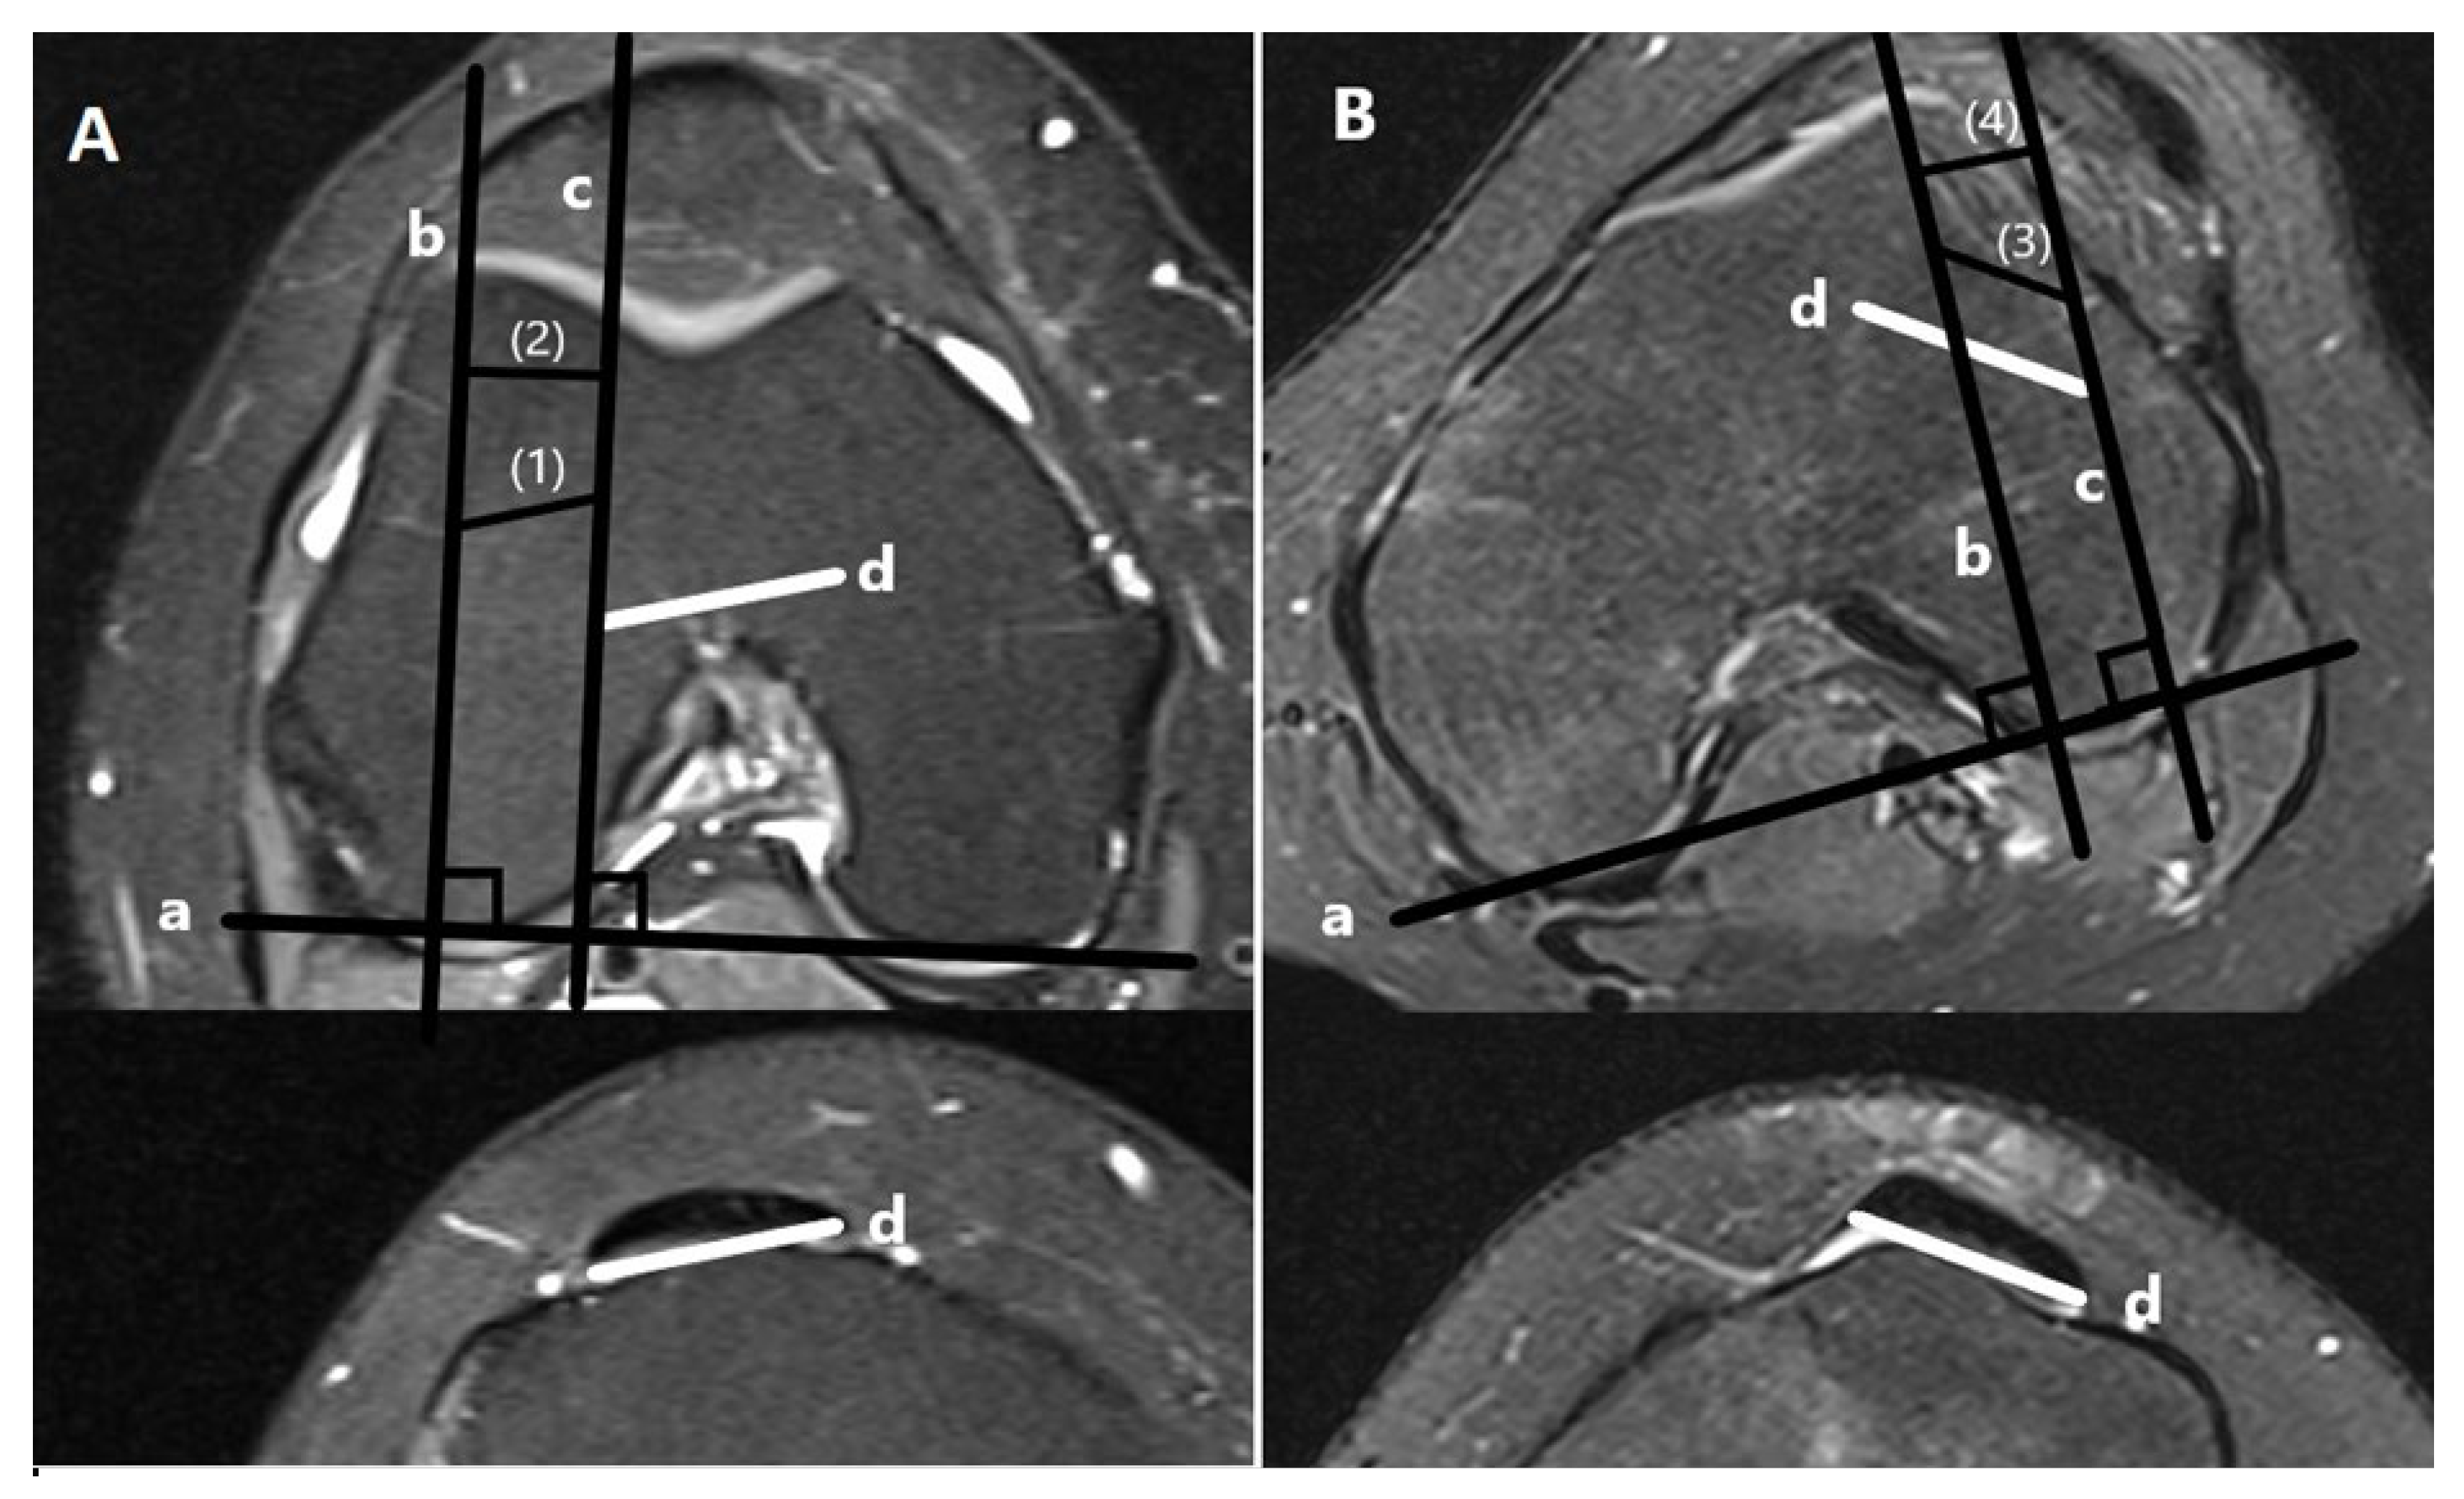

- Trochlear dysplasia measurements

- Lateralization measurements